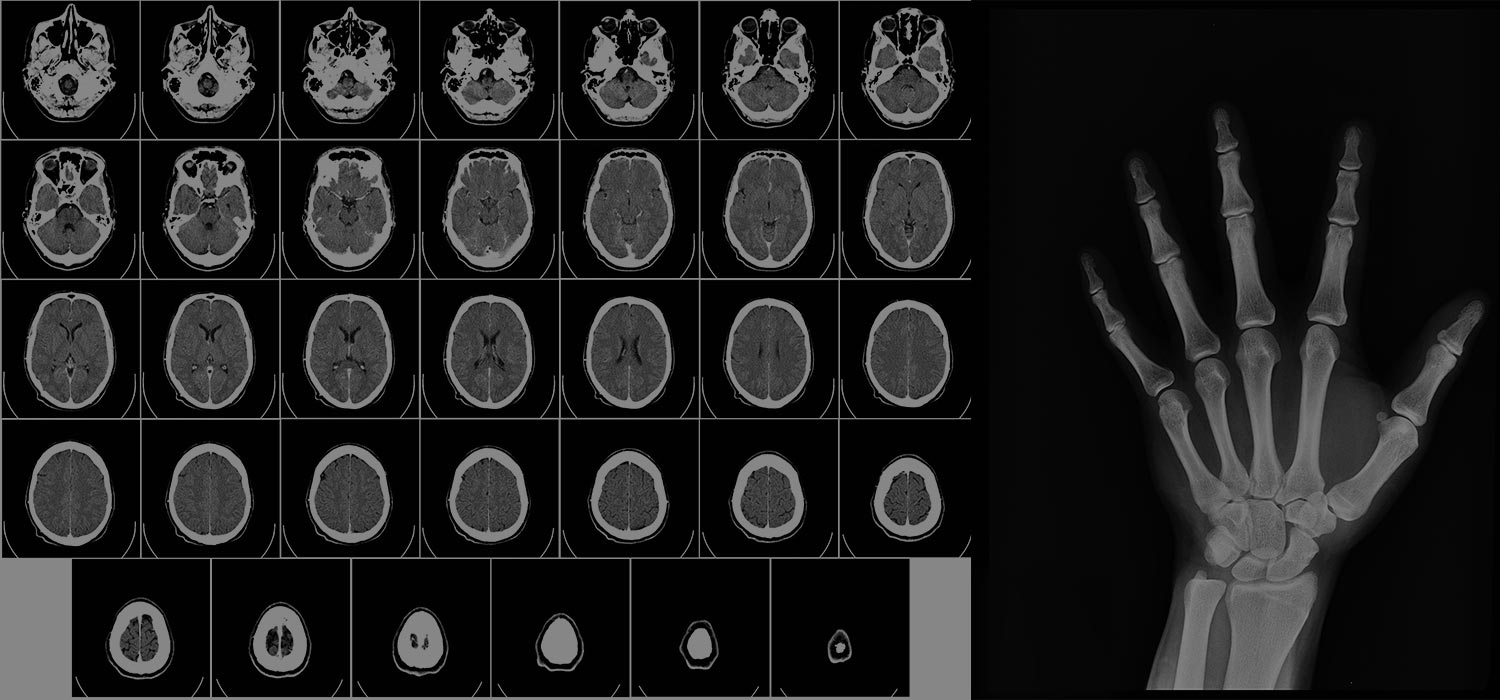

It is important to designate all areas and give examples of the unique and personalised information medical imaging technology provides. Imaging is the first step from clinical symptoms to diagnosis in many diseases. Imaging has played this role for decades. It assesses the location and extent of disease in individual patients, identifies structural abnormalities and physiological milieu, and provides critical information for selecting appropriate treatment.

Medicine will play an increasingly important role. An important goal of PM is to stratify patients into different risk groups to make individualised decisions about prevention and treatment. To this end, there is great potential for using quantitative imaging biomarkers that can characterise perfusion, blood flow, metabolism, and cellularity. However, standardisation and quality assurance measures must be implemented before imaging biomarkers are widely adopted in clinical routine. Differences in imaging modalities and user experiences are important standardisation issues. Radiation genomics and nano theranostics are two emerging fields in which radiology plays an important role. Radiogenomics creates a link between diagnostic imaging and genomic function. A promising new field of nano theranostics is the use of drugs and contrast agents in a single entity, allowing real-time drug delivery and distribution monitoring.